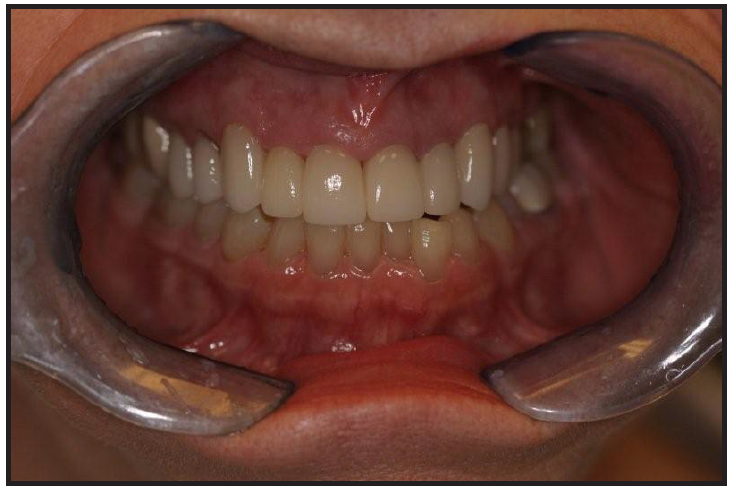

With careful treatment planning and communication, this case exceeded the expectations of the patient who was pleased to no longer consider herself to have a villainous smile (see Figure 7 and Figure 8). Listening to the patient's desires helps to map out a plan of action that will exceed the expectations of the patient and allows for the potential for referrals and future growth for the practice.

Figure 7 – Final Photo Using Retractors

Figure 7

Figure 8 – Final Patient Photo

Figure 8